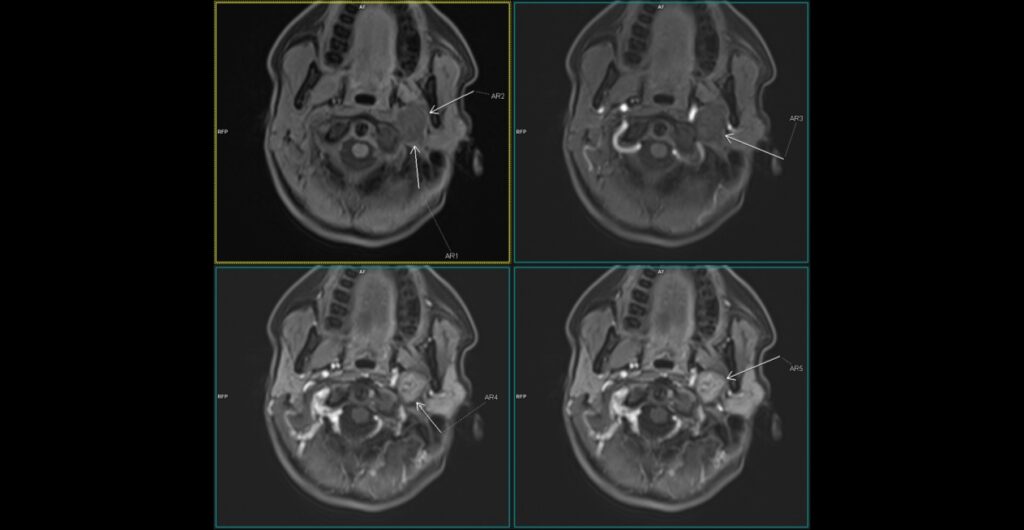

Figura 1: patru imagini în paralel la nivelul regiunii cervicale pentru analiza comportamentului leziunii la administrare dinamică a substanței de contrast la examinarea IRM

Discuţie caz nr 129: pacientul este trimis la examinare IRM cu suspiciune ecografică de adenopatie latero-cervicală. Se evidențiază o leziune rotund-ovalară în hipersemnal T1 și T2 comparativ cu musculatura scheletică, net delimitată, fără restricție de difuzie a apei, cu priză progresivă de contrast, pe traseul nervului vag. Principalele diagnostice diferentiale: glomusul carotic (priza de contrast precoce de tip flash arterial, este situată în vecinătatea bifurcației carotidiene), adnopatie latero-cervicala, chiste de arc branhial.